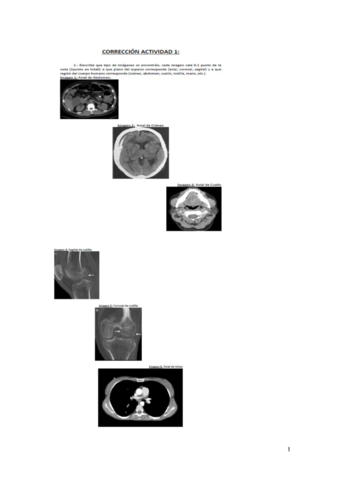

Eixample Clínic - Imagen para el Diagnóstico y Medicina Nuclear

Técnicas de Tomografía Computarizada y Ecografía